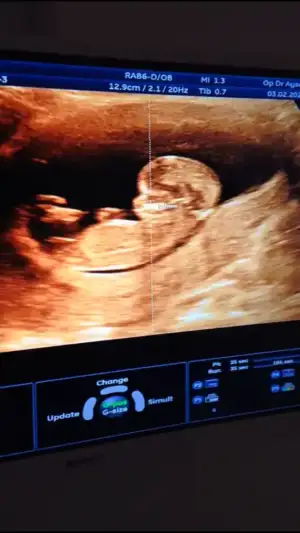

Kız gibi gibi başka usg varsa tekrar tahmin edeyimIkra meyra

Merhaba cinsiyet tahmininde bulunabilir misiniz?Eki Görüntüle 2586799 12+5 haftalık :) şimdiden teşekkürler

Malesef başka yok diğerleri 4 boyutlu çekim teşekkür ediyorum çok mutlu oldumKız gibi gibi başka usg varsa tekrar tahmin edeyim

Kız gibi gibi başka usg varmı nubu tam net degil

Burda kız gibi geldi bana önceki usg erkek gibi duruyordu nubu burada paralel de değil dikte değilIkra meyra canım yine ben 14 haftalık ne diyorsun

Doktorda göstermiyor dedi :) bende kız istiyorum tabi sağlıklı olsumda artık mecbur bekliycez teşekkür ederimBurda kız gibi geldi bana önceki usg erkek gibi duruyordu nubu burada paralel de değil dikte değil![]()